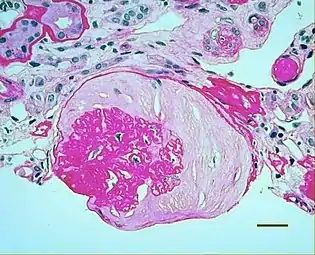

Micrograph showing renal arterial hyalinosis – pink ring right-of-centre. PAS stain.

In the kidneys, as a result of benign arterial hypertension, hyaline (pink, amorphous, homogeneous material) accumulates in the walls of small arteries and arterioles, producing the thickening of their walls and the narrowing of the arterial openings, a process known as arteriolosclerosis. The resulting inadequate blood flow produces tubular atrophy, interstitial fibrosis, and glomerular alterations (smaller glomeruli with different degrees of hyalinization – from mild to sclerosis of glomeruli) and scarring around the glomeruli (periglomerular fibrosis). In advanced stages, kidney failure will occur. Functional nephrons[5] have dilated tubules, often with hyaline casts in the opening of the tubules. Additional complications often associated with hypertensive nephropathy include glomerular damage resulting in protein and blood in the urine.

In benign nephrosclerosis, the changes occurring are gradual and progressive, however, there can be sufficient kidney reserve capacity to maintain adequate kidney function for many years.[9] The large renal arteries exhibit intimal thickening, medial hypertrophy, duplication of the elastic layer. The changes in small arterioles include hyaline arteriolosclerosis (deposition of hyaline, collagenous material), which causes glomerular collapse (wrinkling and thickening of capillary basement membranes and collapse of capillary lumen) and solidification (glomeruli exhibit sclerosis and increase in mesangial matrix). The degree of scarring correlates with the degree of glomerular filtration deficit.